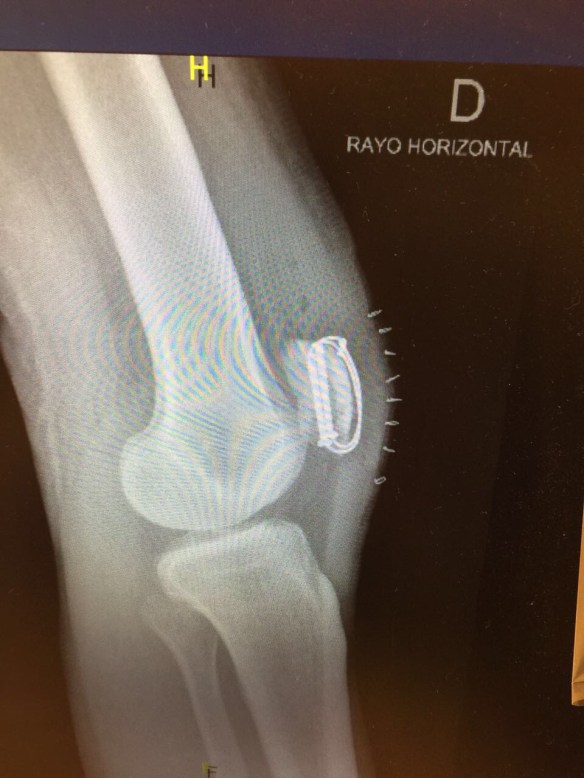

Under gårdagen var jag även på kontrollröntgen och konstaterade att allt såg bra ut och att skruvarna och ståltrådarna placerats som de skulle 🙂

Så tokigt kan det gå när man har otur och faller. Sjukt egentligen hur skör kroppen är när olyckan är framme. Har nog ramlat på skridskor ett hundratal gånger tidigare, men att hela min knäskåla skulle krossas, det är bra mycket otur det. Det kommer bli en lång väg tillbaka och sommaren blir ju långt ifrån vad jag planerat. Kommer inte kunna bli nått spring på akuten då jag kommer vara fast med kryckor och en gradreglerande skena runt benet de första 6 veckorna. Nu är den inställd på 0-30 grader och efter 6 veckor ska jag successivt ha tagit mig upp till 90 grader och kunna bli av med skenan. Sen kommer det dröja ytterligare en tid innan jag kan gå normalt. Får räkna med totalt 6 månaders rehabilitering. Så något maraton i Berlin i september som planerat blir det ju inte 😦